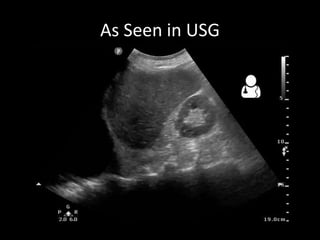

A patient presented with a penetrating chest injury, showing clinical signs of a hemothorax or hemopneumothorax including cyanosis, decreased or absent breath sounds on the affected side, tracheal deviation away from the affected side, dull percussion notes, unequal chest rise, tachycardia, hypotension, and pale, cool, clammy skin. An ultrasound and chest X-ray confirmed a hemothorax or hemopneumothorax, which was treated with insertion of an intercostal drain and assisted ventilation if necessary.